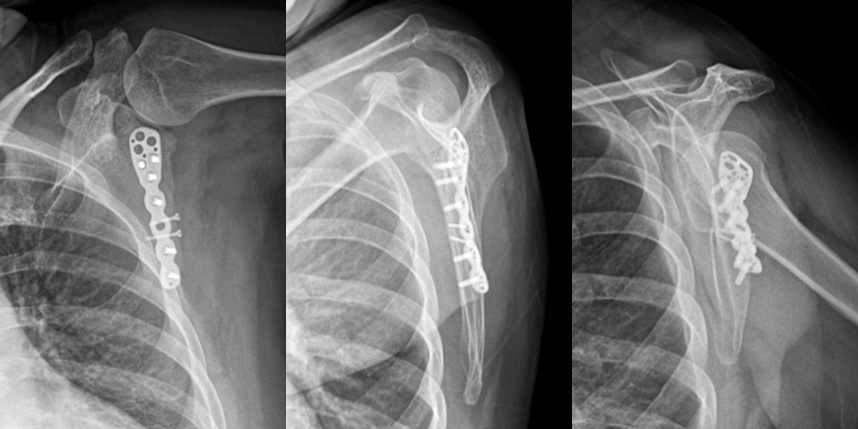

상완골 골절

* 환자에게 받은 소중한 자료입니다.